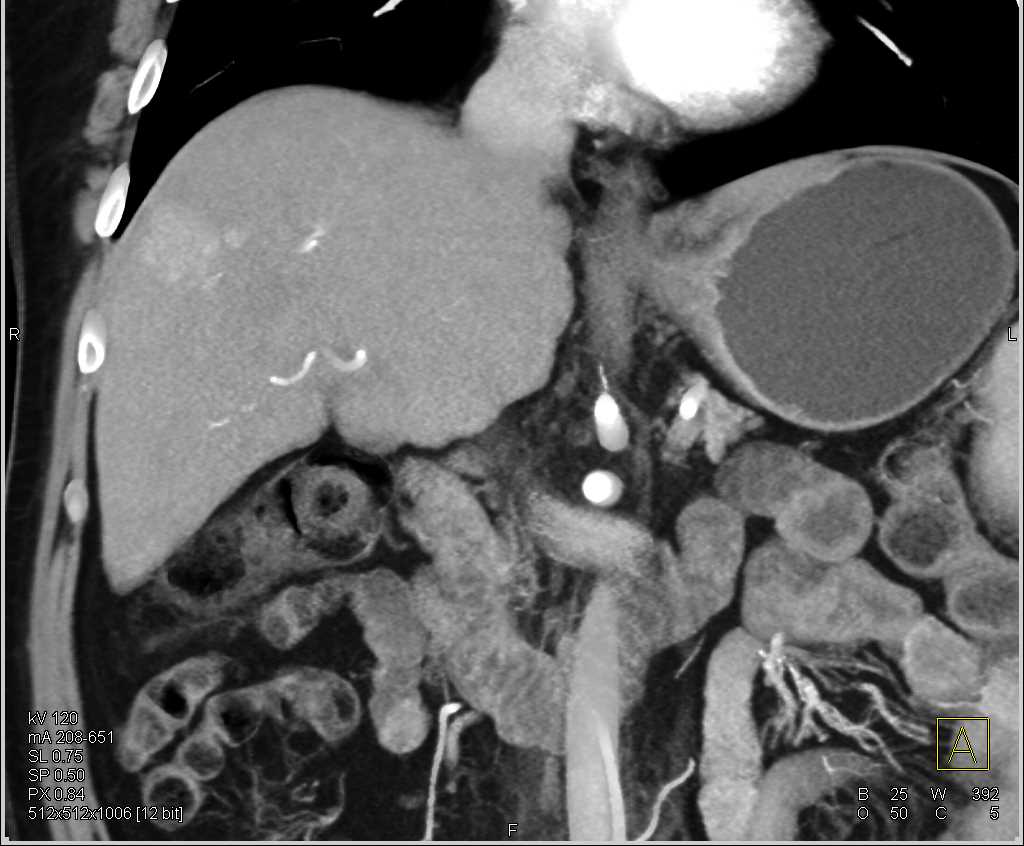

Vascular Lesion in the Right Lobe of the Liver Liver Case Studies What Is Vascular Liver Disease Vascular disorders of the liver, although affecting less than 5/10,000 patients, collectively account for a number of rare conditions that represent an important health problem worldwide in the field of liver diseases. Find out the symptoms of liver disease, when to get medical help and what you. Some of these variants may result in areas of enhancement that can mimic.. What Is Vascular Liver Disease.

Vascular Lesion in the Right Lobe of the Liver Liver Case Studies What Is Vascular Liver Disease Vascular disorders of the liver, although affecting less than 5/10,000 patients, collectively account for a number of rare conditions that represent an important health problem worldwide in the field of liver diseases. Vascular liver disorders, portal vein thrombosis, and procedural bleeding in patients with liver disease [updated november 2020] previous. Vascular liver diseases are disorders of the hepatic vasculature that. What Is Vascular Liver Disease.